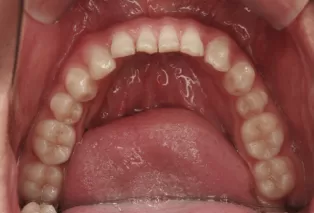

Photos intra-orales